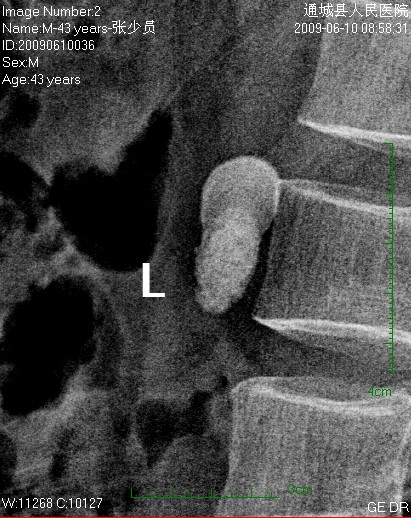

标题: CL1983:尿路结石

这颗石头长得怪,好象有顶帽子戴。

左侧输尿管结石并左肾积水